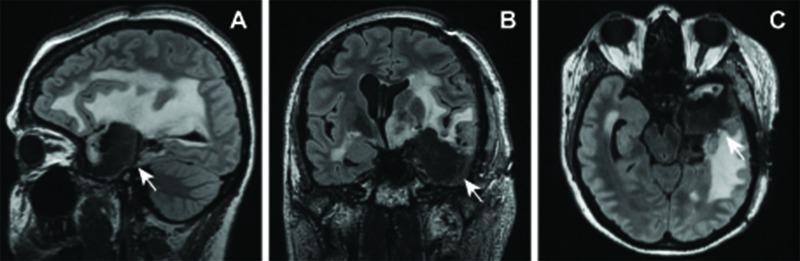

Stereotactic radiosurgery (SRS) is a promising treatment for medically intractable mesial temporal lobe epilepsy. SRS for epilepsy has had an acceptable safety profile with reports of radiation-induced vascular malformations confined to central nervous system pathologies with prominent angiogenesis - namely, primary brain tumors, metastases, and arteriovenous malformations. Theoretical risks for radiation-induced lesions following radiosurgery for epilepsy have yet to be established. Of 13 patients treated in a pilot trial for medial temporal lobe epilepsy, one developed multiple delayed radiation-induced cavernous malformations following radiosurgery. This patient received a prescription dose of 20 Gy delivered to the amygdala, anterior hippocampus, and parahippocampal gyrus. Eight years following treatment, computed tomography imaging demonstrated an evolving hyperdensity in the mesial temporal lobe. Magnetic resonance imaging confirmed multiple T2 hypointense lesions with a mixed-signal intensity core in the left parahippocampal gyrus and anterior temporal lobe. The patient was initially managed conservatively. However, recurrent hemorrhage ultimately caused an acute deterioration in mental status, aphasia, and hemiparesis, necessitating surgical resection. Pathology confirmed radiation-induced cavernous malformations. This represents the first case of a radiation-induced vascular lesion as a long-term sequela of radiosurgery for epilepsy and illustrates the potential for this complication even when low doses are used in patients without angiogenic lesions. Optimal timing and indications for surgical resection of radiation-induced cavernous malformations prior to the development of neurologic symptoms warrant further refinement. Long-term vigilance and clinical monitoring are required.

立体定向放射外科手术(SRS)是治疗药物难治性内侧颞叶癫痫的一种有前景的方法。用于癫痫的SRS具有可接受的安全性,有报告称辐射诱发的血管畸形局限于具有显著血管生成的中枢神经系统病变,即原发性脑肿瘤、转移瘤和动静脉畸形。癫痫放射外科手术后辐射诱发病变的理论风险尚未确定。在一项内侧颞叶癫痫的试点试验中治疗的13例患者中,有1例在放射外科手术后出现了多个延迟性辐射诱发的海绵状畸形。该患者接受了20 Gy的处方剂量,照射杏仁核、前海马体和海马旁回。治疗8年后,计算机断层扫描成像显示内侧颞叶出现逐渐发展的高密度影。磁共振成像证实左侧海马旁回和颞叶前部有多个T2低信号病变,核心为混合信号强度。患者最初采用保守治疗。然而,反复出血最终导致精神状态急性恶化、失语和偏瘫,需要进行手术切除。病理证实为辐射诱发的海绵状畸形。这是首例作为癫痫放射外科手术长期后遗症的辐射诱发血管病变,表明即使在没有血管生成病变的患者中使用低剂量时,这种并发症也有可能发生。在神经症状出现之前,手术切除辐射诱发的海绵状畸形的最佳时机和适应证有待进一步完善。需要长期的警惕和临床监测。